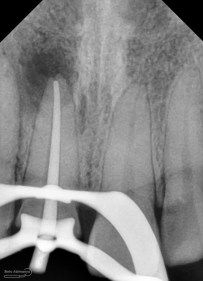

Foto radiografis setelah pengeluaran gutap

Panjang kerja saya ukur menggunakan apex locator dan dikonfirmasi menggunakan ronsen

Foto radiografis konfirmasi panjang kerja

Foto radiografis pengepasan guttap